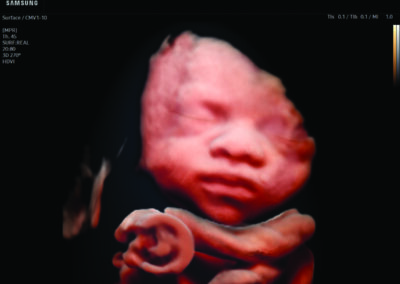

Comprehensive, advanced and expert MFM care for high-risk pregnancies

- Fetal anomalies